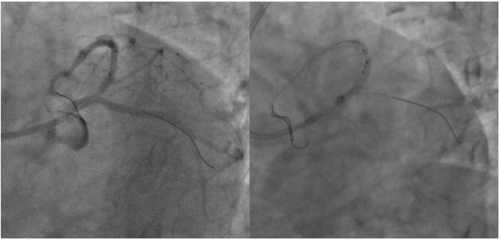

张景昌教授领导的团队对病例进行了多学科的综合分析评估。他们计划通过右侧股动脉入路,首选使用L32号VenusA-Valve瓣膜进行手术。此外,他们还使用了VenusA-Pro第三代可回收输送系统,相较于第二代输送系统,该系统具有更好的推送性和柔顺性。同时,他们对海波管进行了改进,在不降低推送性的同时提高了系统的柔顺性。这些改进旨在确保瓣膜的稳定释放、改善同轴性并降低冠脉风险。在瓣膜释放后,团队会结合造影和超声情况进行观察。

在瓣膜释放完成后,立刻进行了造影和超声评估。结果显示,患者跨瓣压差显著降低,超声检查没有发现瓣周漏,全主动脉和入路也没有出现并发症。手术圆满成功。

术中片段: